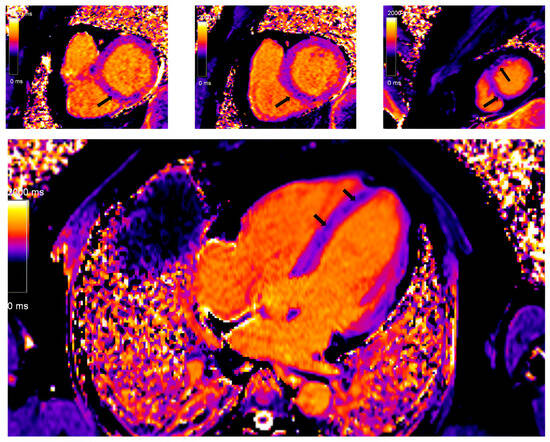

5.4. Cardiac Magnetic Resonance (CMR)